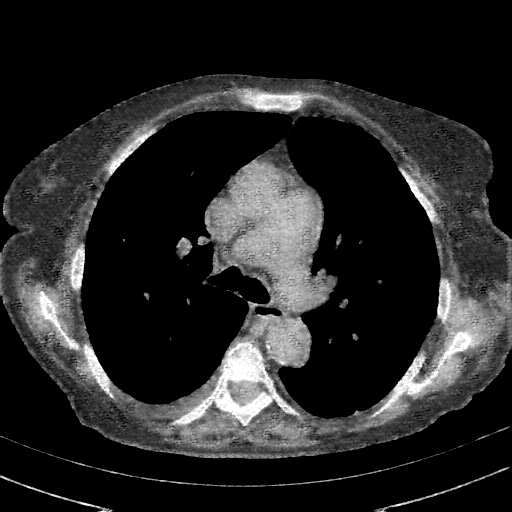

Generated VENOUS CT scan (A→B translation)

Full window (WL 1023.5, WW 4095 β†’ Low βˆ’1024, High +3071)

Mediastinum window (WL 40, WW 400 β†’ Low βˆ’160, High +240)